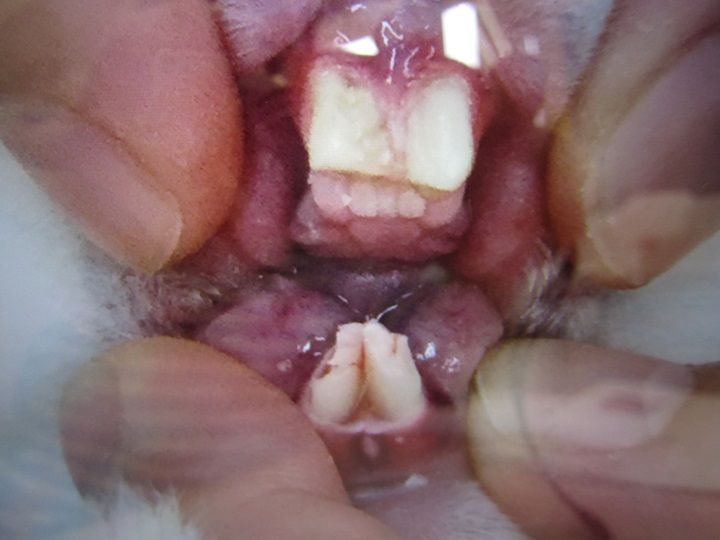

話を戻し、まずは切歯の状態から

処置前

伸びが早く感じるのと、下手に擦れてる感あり

処置後

今回は2週間寄りの間隔だったのにな…。